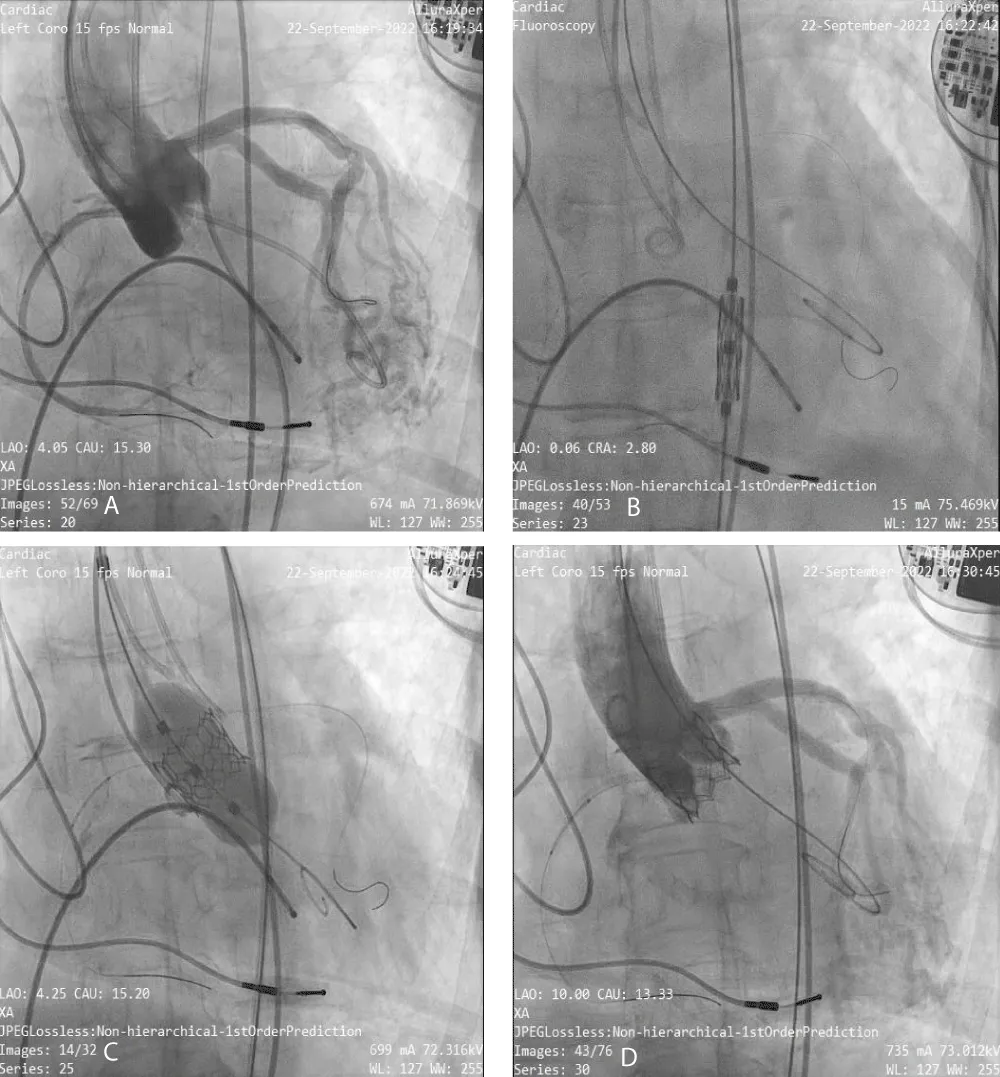

The MSCT scan showed Coronary Arteries (CA) with low heights (right CA: 7.4 and left CA: 8.7 mm) (Figure 1). The patient was considered suitable for transfemoral TAVR as per the Heart Team’s decision and a 20 mm BE Myval THV was selected in consideration of the low coronary heights. Written informed consent was obtained from the patient and the family.

Figure 1: Computed Tomography images shows- A) Right coronary artery height, B) Left coronary artery height, C) Aortic annulus area, D) Aortic valve calcification and E) Deployment angles.